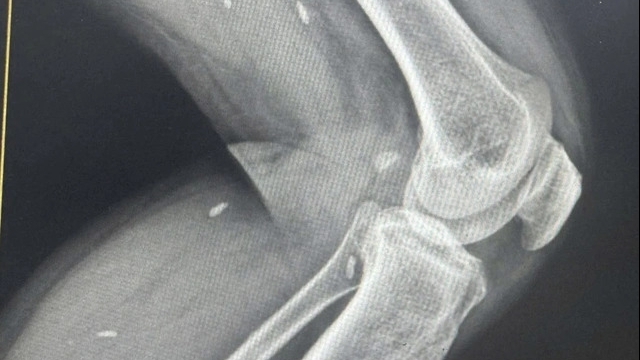

| Bé gái đã cai được máy thở, cai oxy, đang theo dõi chức năng thận. (Ảnh: VTV) |

Trước đó, bé gái vào nhập viện trong tình trạng nguy kịch, theo dõi nhiễm khuẩn huyết, sốc nhiễm khuẩn, suy chức năng đa cơ quan.